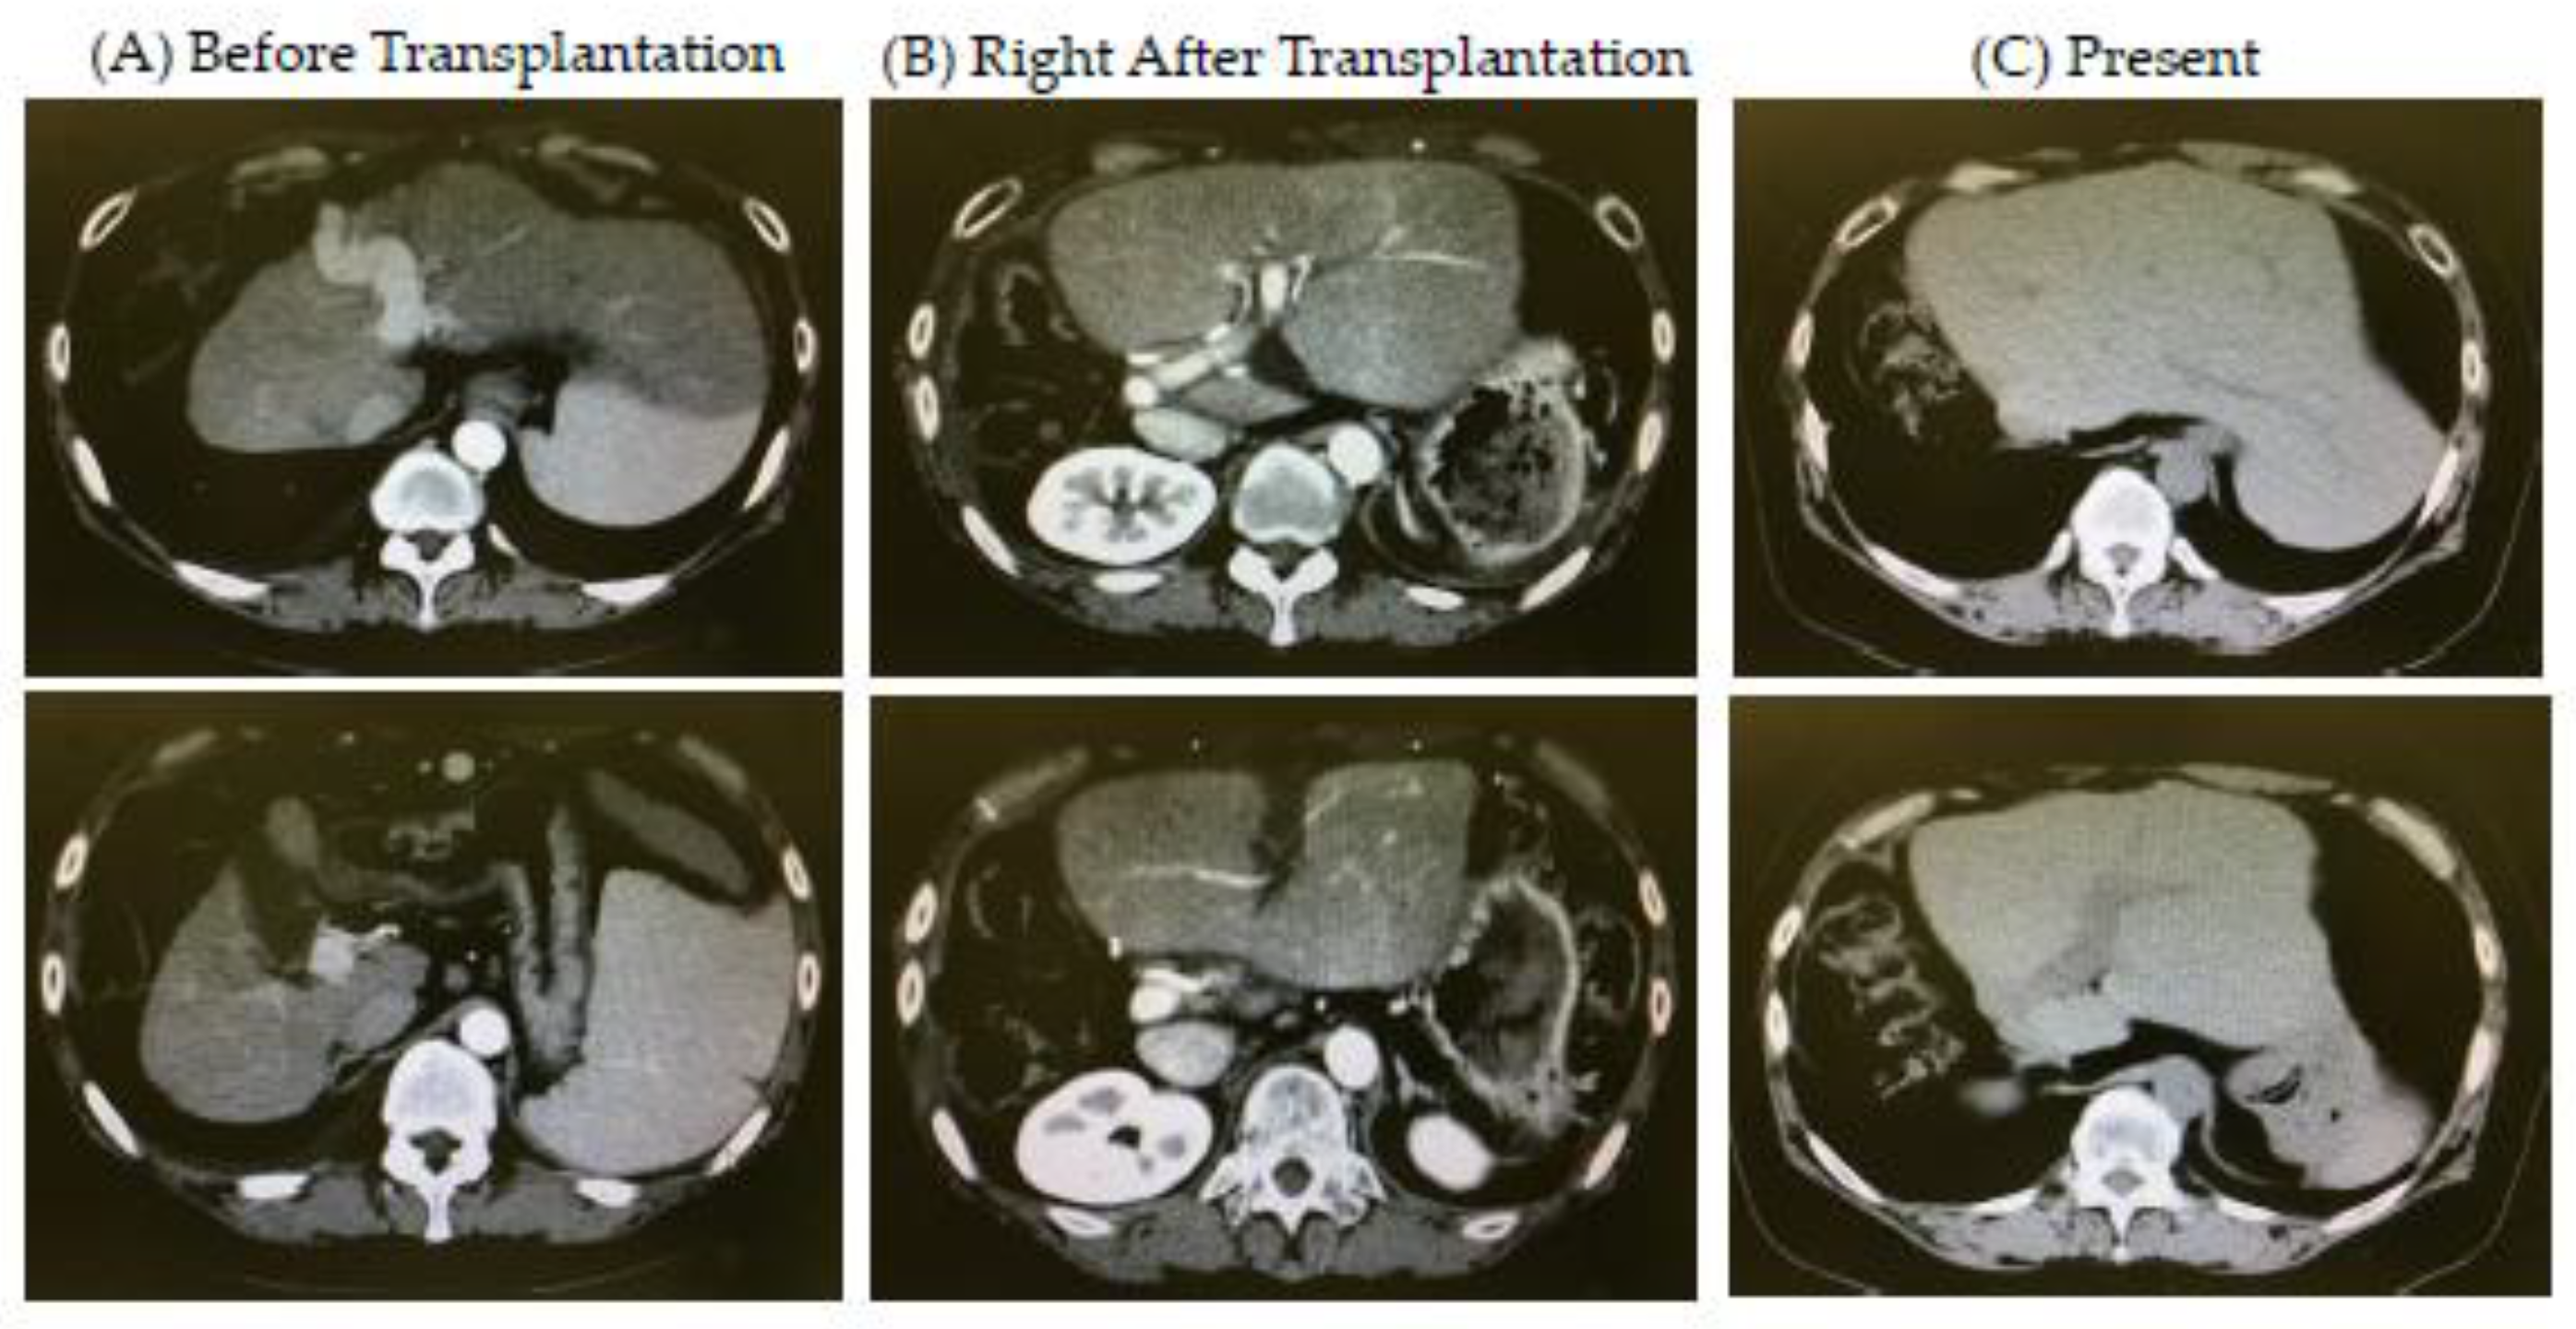

2.1. Case

2.2. Donor and Living-Donor Liver Transplantation (LDLT)